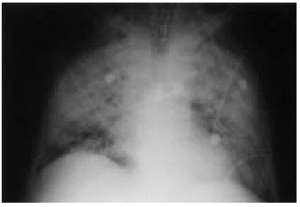

Se trataba de un paciente de 44 años con antecedentes de pancreatitis biliar, cirrosis hepática e insuficiencia hepática grave de origen enólico, que se hallaba en lista de espera para trasplante hepático. Dos meses antes del ingreso se inició tratamiento con 40 mg/día de prednisona oral por un brote de hepatitis aguda alcohólica. Ingresó por una descompensación hepática de etiología multifactorial, con insuficiencia renal aguda, hiponatremia, hipercaliemia, ictericia, ascitis, alteración de la coagulación, anemia y leucocitosis sin un foco infeccioso claro, con cultivos de orina y líquido ascítico negativos. Se realizó una paracentesis evacuadora y se inició tratamiento con una transfusión de concentrados de hematíes y plasma, vitamina K, omeprazol, enemas de lactulosa, cefotaxima y una pauta descendente de corticoides. A las 2 semanas de evolución, con una dosis de prednisona de 10 mg/día, presentó fiebre, con tos y expectoración escasa, disnea e hipoxemia. En la radiografía de tórax se observaban infiltrados alveolares en ambas bases. Se inició oxigenoterapia con FiO2 al 50% y se cambió el tratamiento antibiótico a imipenen, eritromicina y vancomicina. En la exploración se observó que el paciente estaba consciente y orientado, hemodinámicamente estable, con una presión arterial de 100/60 mmHg, una frecuencia cardíaca de 100 lat/min, con fiebre, ictericia cutaneomucosa, desnutrición con atrofia muscular, taquipnea, disnea, ascitis y edemas generalizados. En la auscultación cardiopulmonar se apreciaban crepitantes difusos, tonos cardíacos rítmicos y ausencia de soplos. Progresivamente, el paciente evolucionó a insuficiencia respiratoria grave, con gran trabajo respiratorio y aumento del gradiente alveoloarterial de oxígeno. En la radiografía de tórax se apreciaba una opacidad alveolar bilateral difusa de distribución perihiliar (fig. 1). En la analítica destacaba: hemoglobina 9,2 g/dl, hematócrito 27,5%, plaquetas 67,000/μl, leucocitos 19 x 106/l (neutrófilos 15,9 x 106/l, linfocitos 1,9 x 106/l, monocitos 0,2 x 106/l, cayados 1,1 x 106/l), glucemia 103 g/dl, creatinemia 1,6 mg/dl, urea en plasma 132 mg/dl, natremia 133 mEq/l, calemia 4,9 mEq/l, actividad de protrombina 19%, TTPA 60,3 s, INR 4,81 y fibrinógeno 68 mg/dl. Se inició ventilación mecánica no invasiva y, ante los signos de fracaso ventilatorio, se procedió a intubación y ventilación mecánica. Se realizó broncoscopia con toma de muestras para lavado broncoalveolar (LBA) y catéter protegido telescopado (CPT), visualizándose quistes de P. carinii. La reacción en cadena de la polimerasa (PCR) del ADN de P. carinii fue positiva. La serología para VIH fue negativa. Con el diagnóstico de neumonía por P. carinii se retiraron los antibióticos previos y se inició tratamiento con trimetropin a dosis de 20 mg/kg/día y sulfametoxazol a dosis de 100 mg/kg/día. A pesar de no existir linfopenia, se cuantificaron las cifras de linfocitos CD4+ y CD8+, que estaban dentro del rango normal: CD4 1.098,3/μl, CD8 468/μl y CD4/CD8 2,35/μl. El paciente presentó una mala evolución, con insuficiencia respiratoria refractaria, neumotórax izquierdo y disfunción multiorgánica, y finalmente falleció. Se realizó un estudio necroscópico y, tras el correspondiente estudio anatomopatológico, se confirmó el diagnóstico de cirrosis hepática y neumonía bilateral por P. carinii al observarse quistes en muestras de tejido pulmonar (fig. 2). No se encontró ninguna otra causa de inmunodepresión.

Figura 1. Radiografía de tórax: opacidad alveolar bilateral difusa de distribución perihiliar.